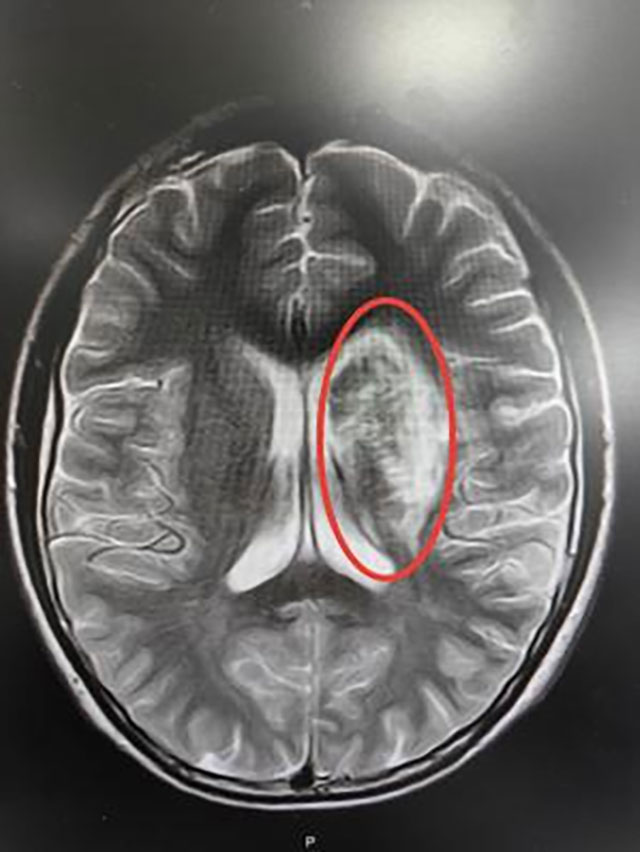

据媒体报道,阿东(化名)暑假期间兼职时,每天连续低头洗碗、擦桌子4小时以上,下班后又趴在床上打游戏、刷短视频2到3小时。这天,阿东突然感到手脚及颈后背常有麻木疼痛感,几天后,麻木感加剧,甚至出现双下肢无法动弹、失去感觉的状况。到医院检查时...